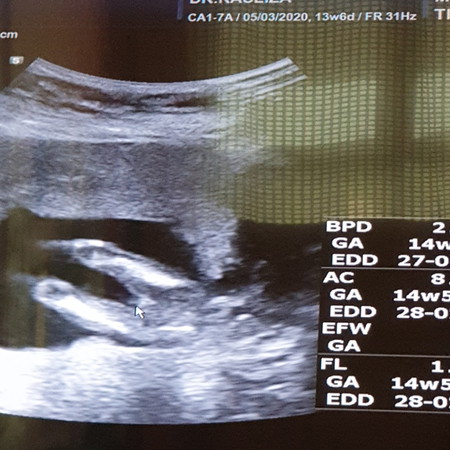

Hi mommies..smlm mcm biasa sy gi chkup kat kpj..kndungn hmpir 15w..mmg x tpikir nk tnya psl gnder..sbb sy dah pasrah..bertahun berusha utk dptkn gel msih blum Allah rzekikan..ini kali yg ke 5..msa scan borak2 ngn doc ..lps tu ttba die ckp inshaa allah kali ni gegel..sy ckp dah leh nmpk ke doc??die ckp 14w dah complete smua..tgok ni..mendatar je..klu boy dah boleh nmpk pistol dah ni..sy cuma ckp alhmdulillah..mmg die seorg pakar..n die jugk mnymbut ksmua bboi sy..scan die sblm ni xpnh silp..tp sy dah bnyk kli gagal..sy xmau gmbira trlalu awal...slgi x lahir sy susah nk pcya..sy akn trus brdoa dan brdoa.. Mummy2 smua tlg doakn utk sy ye..klau bnar kli ni ggel..doakn sy mmpu mmikul amanah Allah ni dgn baik..doakn bby ni mmbsar dgn sihat smpurna..trhindar dari sbrg pnykit..